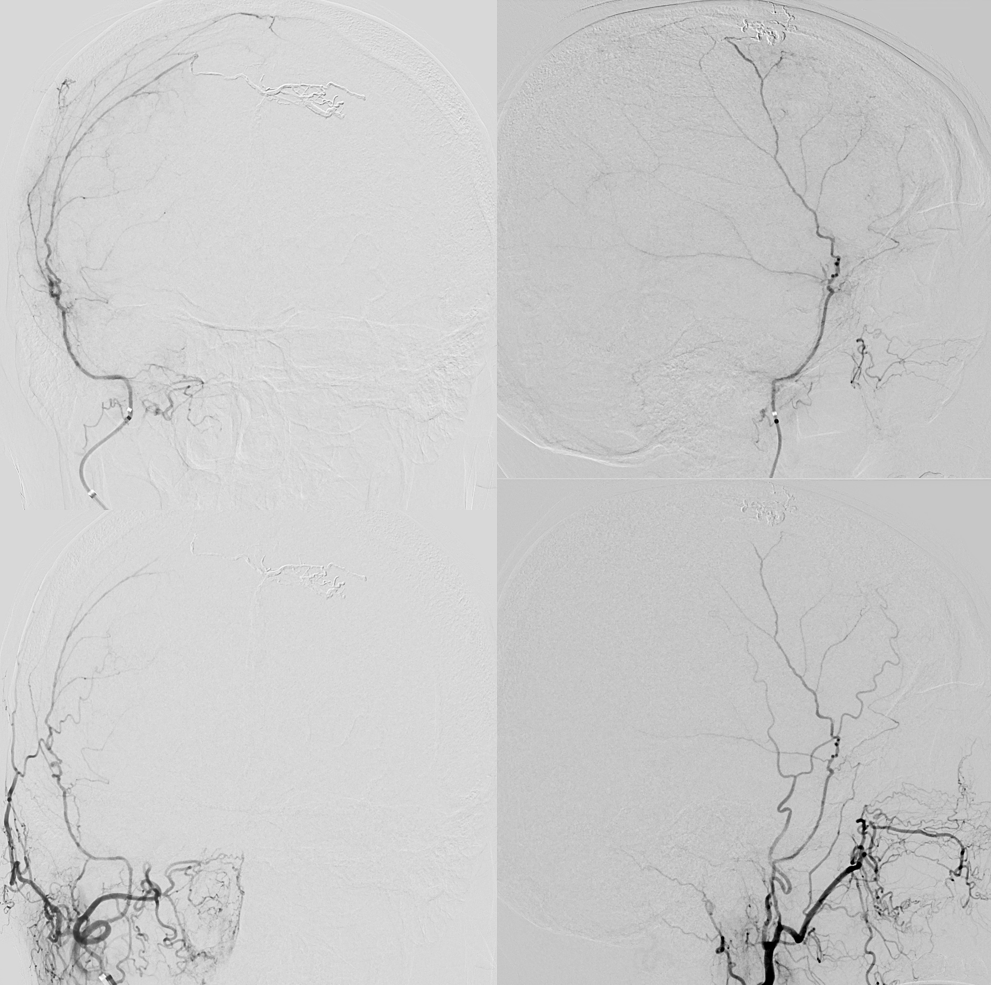

The MMA remains recanalized — better than ever…